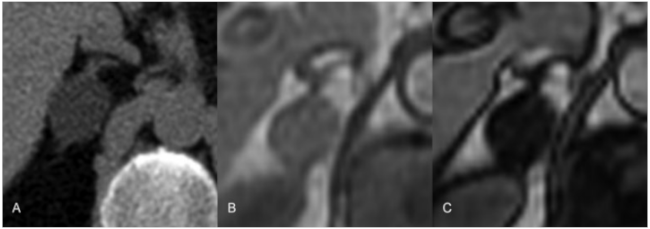

Adenoma suprarrenal en un paciente con MEN tipo 1. La TC sin contraste intravenoso (A) mostró una lesión nodular en glándula suprarrenal derecha con valores densitométricos inferiores a 10UH. En las imágenes de resonancia magnética (RM) en fase (B) y fase opuesta se objetivó pérdida de intensidad de la señal en fase opuesta, característica de los adenomas suprarrenales.